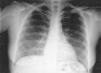

Hemoptisis en mujer de 42 años

Hemoptysis in 42 year old woman